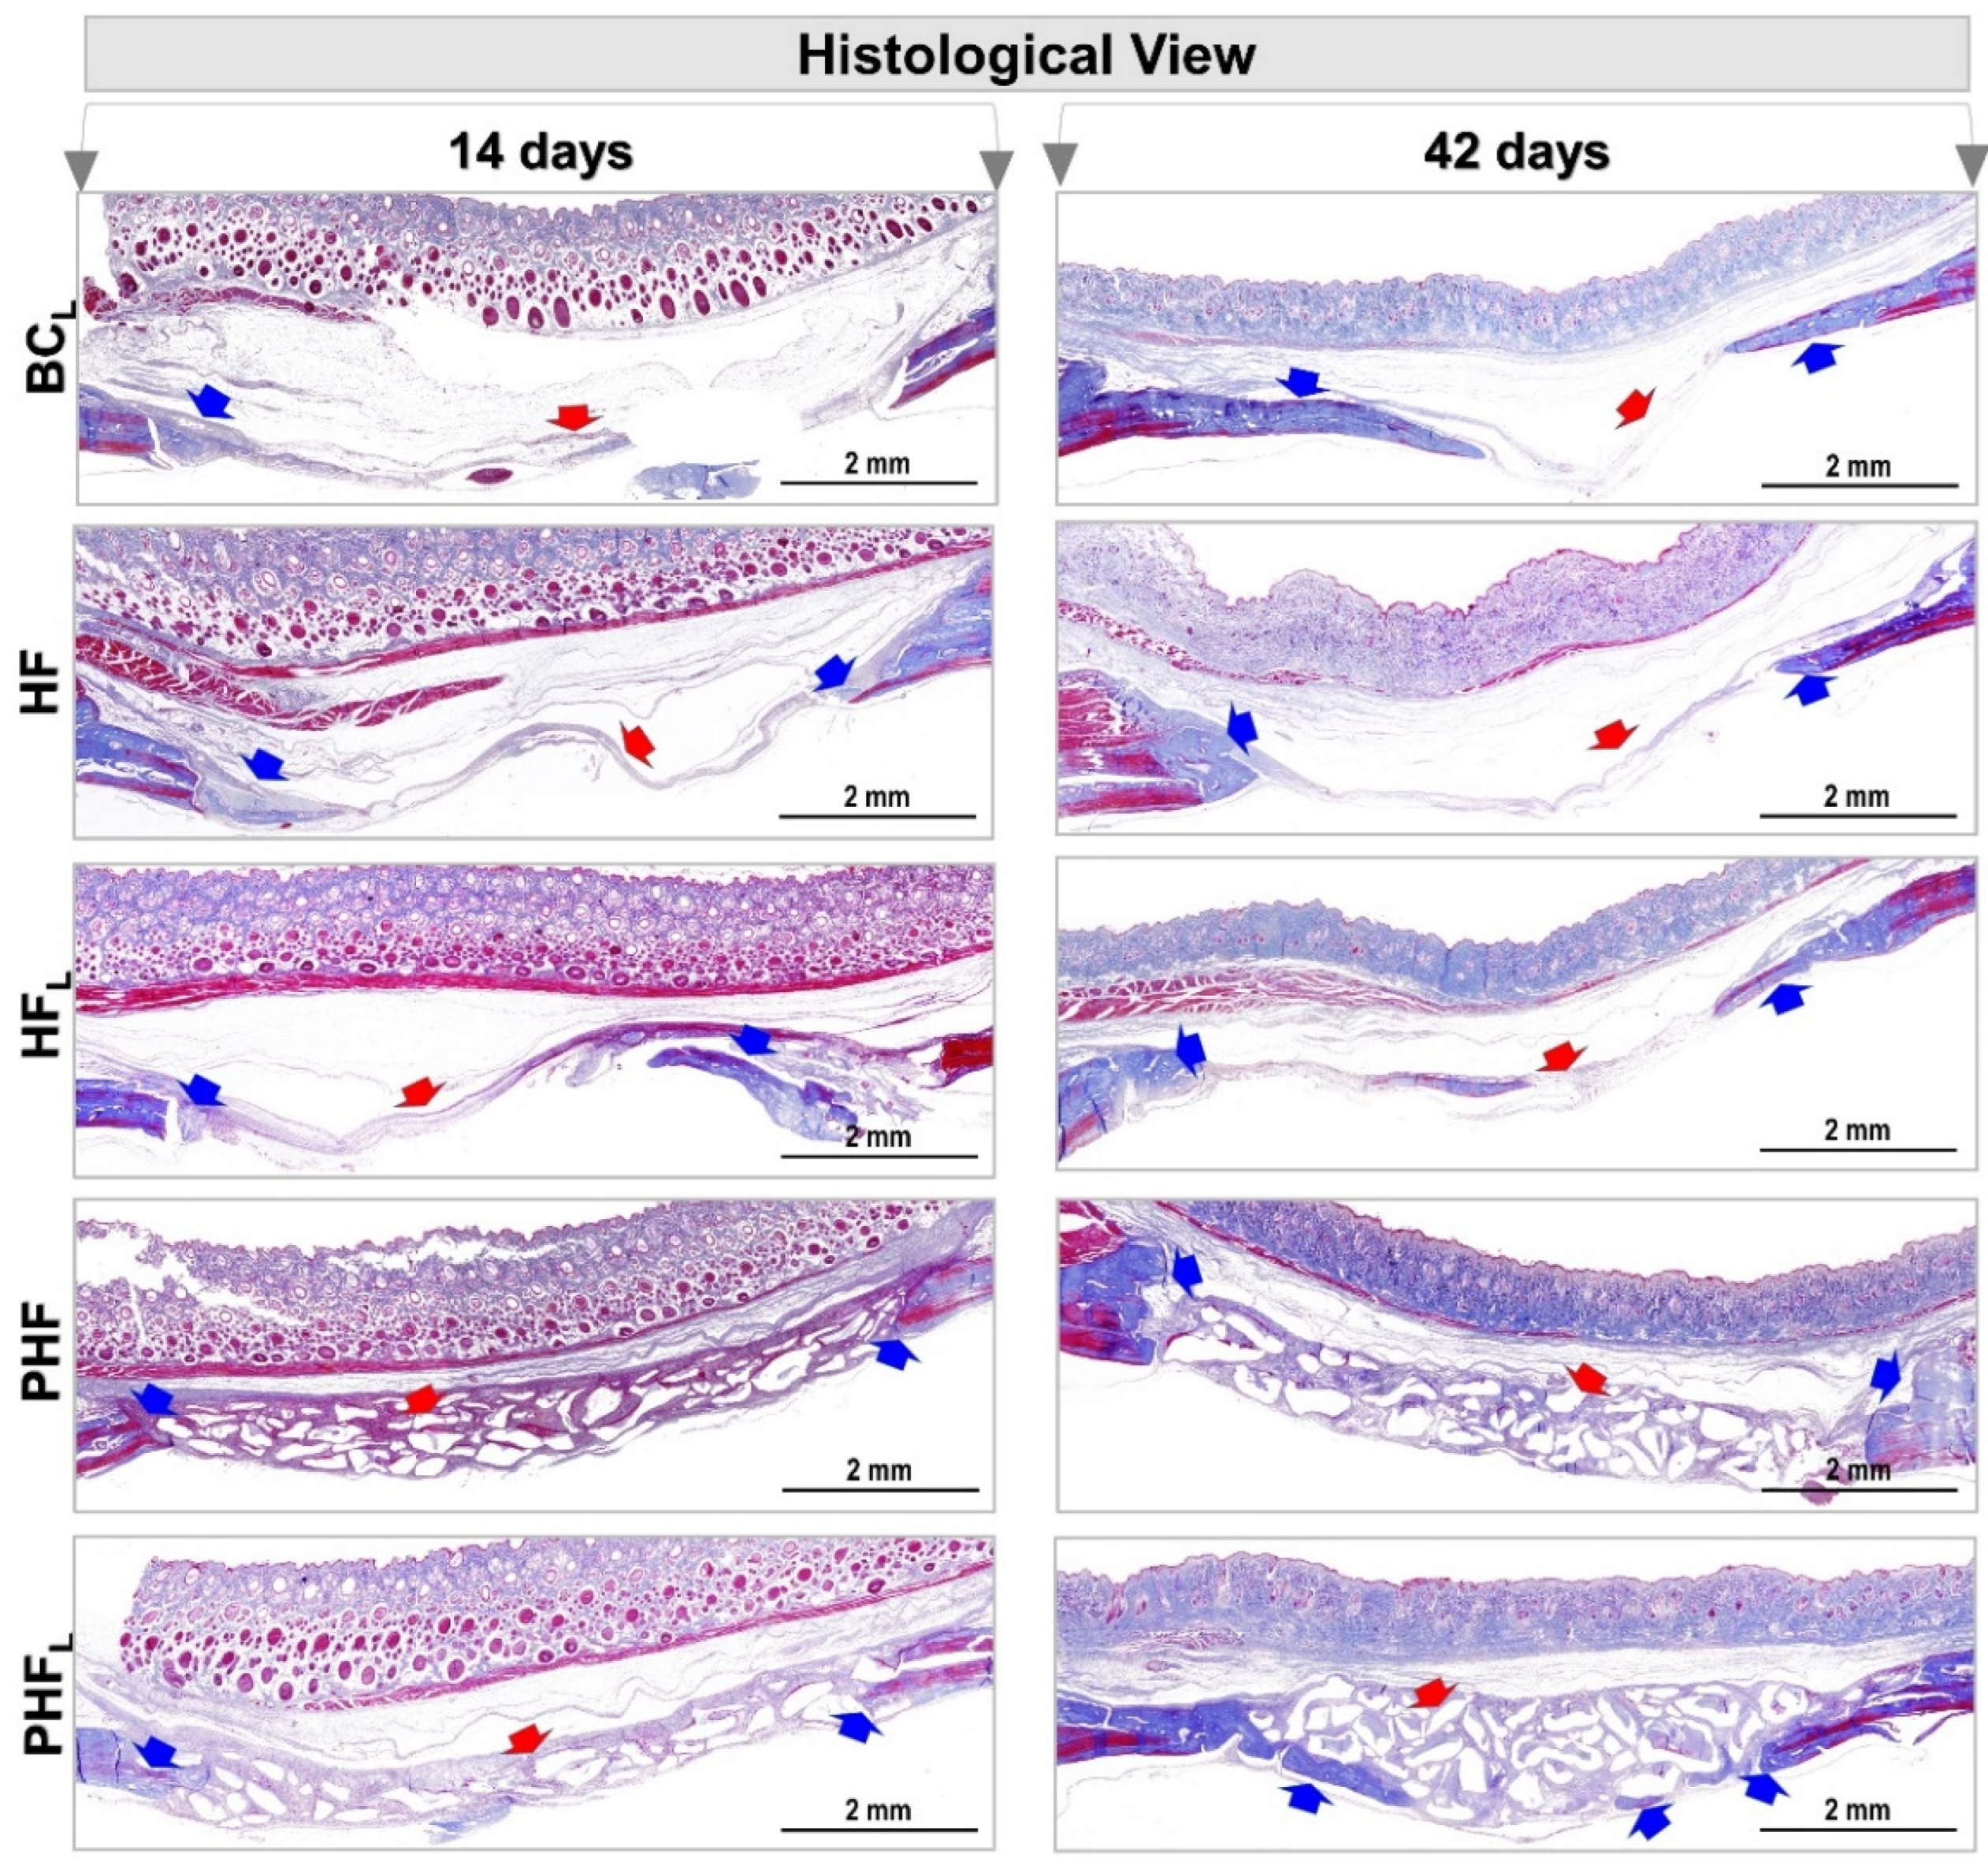

2.3. Birefringence Analysis of Collagen Fibers in Bone Neoformation

4.10. Birefringence Analysis of Collagen Content of Bone Defects